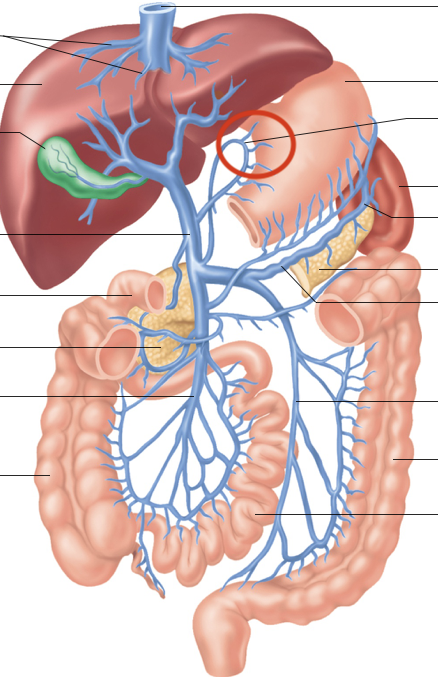

Hepatic Portal System (illustration)

hepatic portal vein

superior mesenteric-small intestine, first half colon

gastric-stomach

splenic-spleen and pancreas

inferior mesenteric-second half colon

hepatic veins